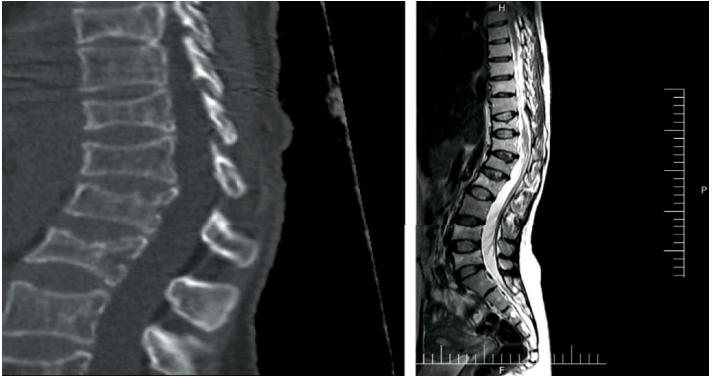

24岁女性患者,主诉严重腰痛。目前正在接受非甾体抗炎药(NSAIDs)和理疗,但疼痛并没有得到减轻。胸腰段X线显示T11-L5椎体高度降低。MRI显示在同一区域,多处压缩性骨折(图1)。应用双能X线骨密度仪(hologicdiscovery系统)对脊柱和髋关节的骨密度进行定量分析。骨密度证实了骨质疏松。此外,患者还有腹痛和贫血。胃肠道检查和相关试验均正常,血液检查显示存在缺铁性贫血。

图1. 患者的影像学结果显示(T11-L5)椎体骨折